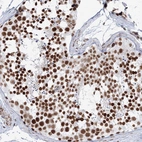

Immunohistochemical staining of human testis shows strong nuclear positivity in cells in seminiferous ducts.